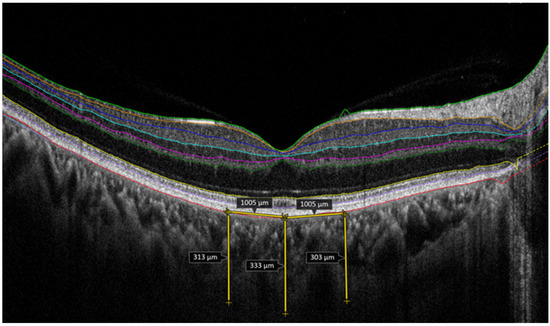

Temporal Arcuate Relaxing Retinotomy for Persistent Full-Thickness Macular Holes: Anatomical and Functional Assessment

Background: Evidence guiding secondary repair of persistent full-thickness macular holes (FTMHs) remains limited and heterogeneous. Temporal arcuate relaxing retinotomy has been described as a salvage maneuver intended to increase temporal retinal compliance, yet functional safety data are scarce. We report consecutive real-world outcomes [...] Read more.

Background: Evidence guiding secondary repair of persistent full-thickness macular holes (FTMHs) remains limited and heterogeneous. Temporal arcuate relaxing retinotomy has been described as a salvage maneuver intended to increase temporal retinal compliance, yet functional safety data are scarce. We report consecutive real-world outcomes of temporal arcuate relaxing retinotomy for persistent FTMHs after failed standard repair(s). Methods: Retrospective consecutive case series of patients with persistent FTMH after ≥1 pars plana vitrectomy (PPV) with internal limiting membrane (ILM) peeling, treated with repeat PPV and temporal arcuate relaxing retinotomy. Outcomes included OCT (Optical Coherence Tomography)-confirmed closure after gas absorption and best-corrected visual acuity (BCVA, logMAR), ellipsoid zone (EZ) status, retinotomy-site morphology on OCT/fundus autofluorescence (FAF), and safety/functional outcomes (systematic scotoma symptom inquiry; Humphrey visual field testing when feasible). Exact binomial 95% confidence intervals (CI) were calculated for proportions. Results: Nine eyes (median age 70 years; range 55–76) underwent temporal arcuate relaxing retinotomy for persistent FTMH. Minimum linear diameter ranged 412–1037 µm (median 613 µm). OCT-confirmed closure was achieved in 7/9 eyes (77.8%; 95% CI 40.0–97.2) at a mean follow-up of 5.9 months (range 2–12). BCVA improved in 8/9 eyes (88.9%; 95% CI 51.8–99.7); mean BCVA improved from 1.26 ± 0.51 logMAR pre-operatively to 0.61 ± 0.18 logMAR at last follow-up (mean change −0.64 logMAR; Wilcoxon signed-rank test p = 0.011). As a sensitivity analysis, the paired t-test yielded p = 0.008. Humphrey visual fields were obtained in 6/9 eyes; one patient reported a new paracentral nasal scotoma, which was subjectively well tolerated. Conclusions: In this small consecutive series, temporal arcuate relaxing retinotomy was associated with a 78% closure rate and mean BCVA improvement in eyes with persistent FTMH after failed standard repair(s), with limited symptomatic scotoma reporting in those assessed. Given the retrospective design, small cohort, and incomplete standardized functional testing, larger comparative studies with uniform functional endpoints (microperimetry, RNFL/GCL metrics, and systematic perimetry) are needed to define patient selection, reproducibility, and relative performance versus contemporary salvage options. Full article